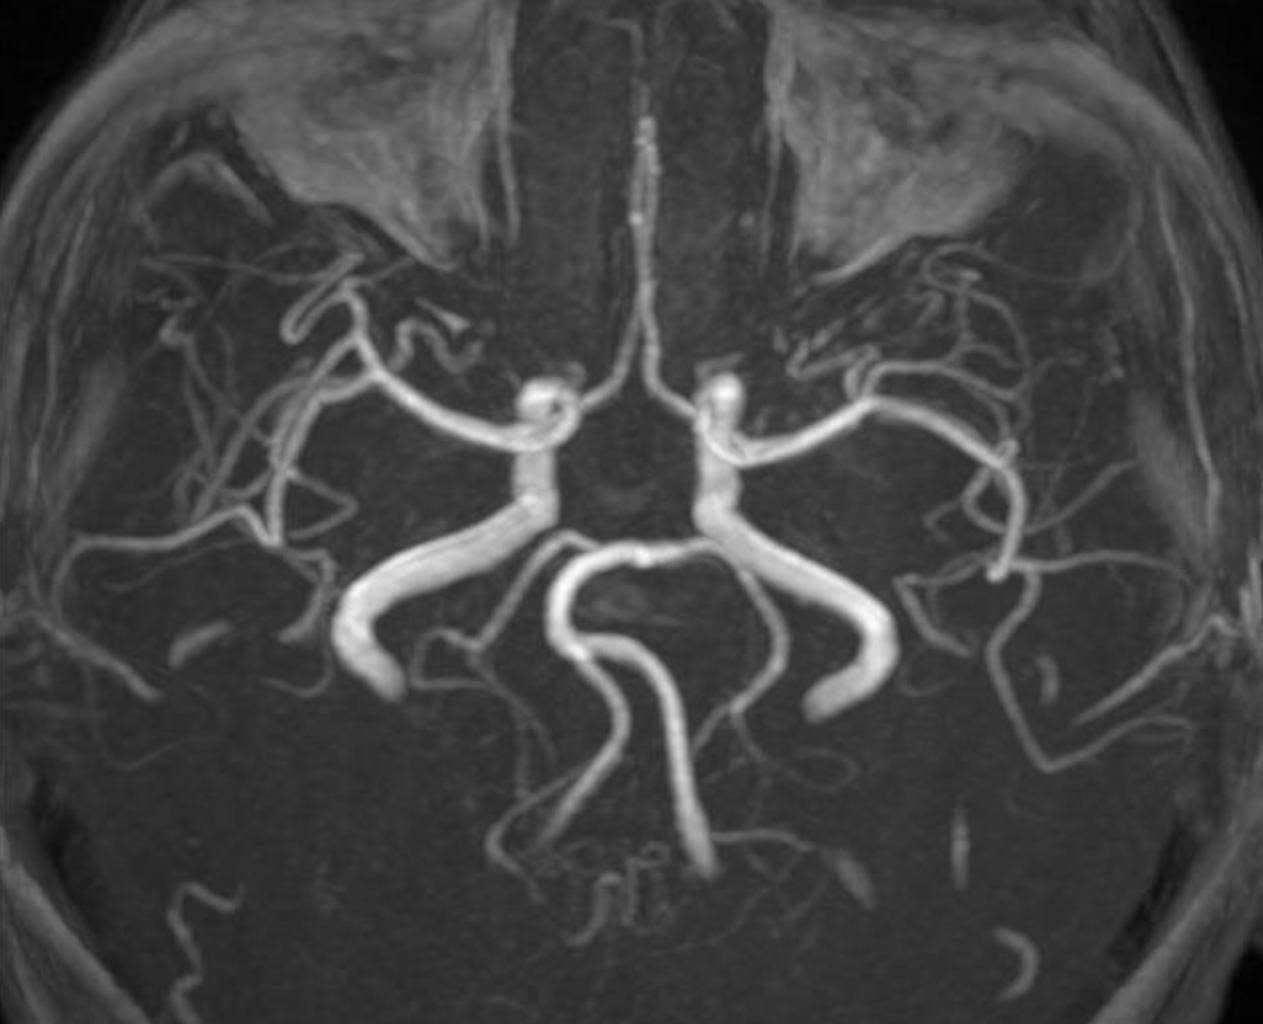

PGS Huy Thắng cho biết, ngay khi nhập viện, người bệnh được chụp MRI não. Hình ảnh cho thấy tổn thương não xảy ra ở hai bên trung tâm bán bầu dục và vùng lồi thể chai. Các thăm dò mạch máu não không ghi nhận tình trạng tắc hay hẹp các động mạch lớn. Dựa trên lâm sàng và hình ảnh học, các bác sĩ chẩn đoán bệnh nhân bị nhồi máu não cấp vùng trung tâm bán bầu dục hai bên và lồi thể chai.

“Vùng trung tâm bán bầu dục, theo Louis Caplan - Giáo sư Thần kinh học tại Trường Y Harvard chính là vị trí ưa thích của những huyết khối nhỏ nhắm đến, đặc biệt khi bệnh nhân có tổn thương nhiều vùng chi phối mạch máu (trung tâm bán bầu dục 2 bên và lồi thể chai thuộc chi phối hệ cảnh - não giữa 2 bên và động mạch não trước hoặc động mạch não sau). Ngoài thuyên tắc huyết khối, trung tâm bán bầu dục là vùng giáp ranh cũng là vị trí tổn thương phù hợp với cơ chế giảm tưới máu”- PGS Huy Thắng giải thích thêm.